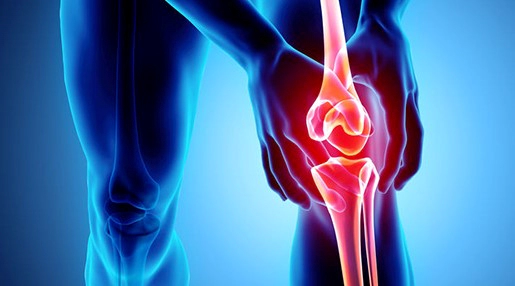

2. 무릎 관절염 치료법

2.1. 약물 치료

통증과 염증을 줄이기 위해 비스테로이드성 소염진통제(NSAIDs), 아세트아미노펜, 코스테로이드 등의 약물이 처방될 수 있습니다. 중증의 경우, 오피오이드 계열의 진통제가 필요할 수도 있습니다. 약물 치료는 의사와 상의하여 적절한 용량과 사용 방법을 결정해야 합니다.

2.5. 관절 주사

염증이 심한 경우, 코르티코스테로이드나 히알루론산 주사를 무릎 관절에 직접 주입하여 증상을 완화시킬 수 있습니다. 이러한 주사는 일시적인 효과를 제공하며, 의사의 지시에 따라 반복하여 시행할 수 있습니다.